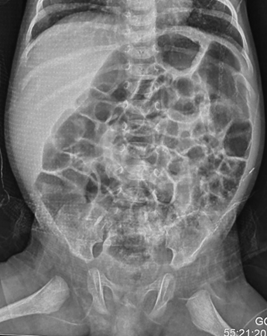

In infants under one year of age, the normal gas pattern on an abdominal X-ray appears honeycomb or polygonal shaped throughout the abdomen (Figure 1).3,4

Figure 1 Anteroposterior supine radiograph in a normal neonate on day-3 of birth showing honeycomb or polygonal gas pattern throughout the abdomen with gas visible in the rectum. It is difficult to differentiate small from large intestine in the neonatal period.